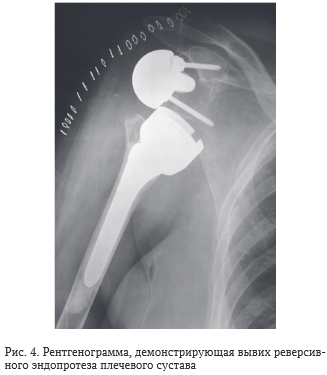

Реверсивное эндопротезирование

Реверсивное эндопротезирование 132 фото